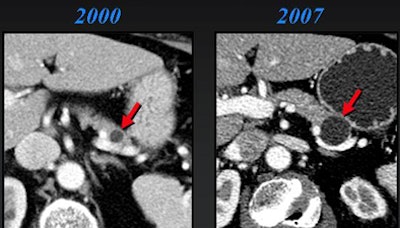

Worrisome features for malignancy are solid tissue within the cyst, obstruction of the main pancreatic duct ≥ 1 cm or the common bile duct, regional lymphadenopathy, or interval enlargement of a lesion, Jeffrey said.

"The presence of solid tissue within cystic lesions in addition to regional lymphadenopathy and interval enlargement are all very significant features suggesting malignancy," Jeffrey said.

Nineteen of the 156 patients had surgery, while only three cases were malignant, Jeffrey said. Most important, all malignancies had solid tissue within the lesion at CT. Interval growth was also a predictor. Lesions grew in seven cases, including two of the three malignancies, Jeffrey said of the study (Abdominal Imaging, January-February 2007, Vol. 32:1, pp. 119-125).

"The take-home message here is that those that have solid internal tissue or enlarge over time have potential for malignancy," he said. "Interval growth was seen in seven cases, two of which were malignant, so obviously benign lesions can also grow over time."